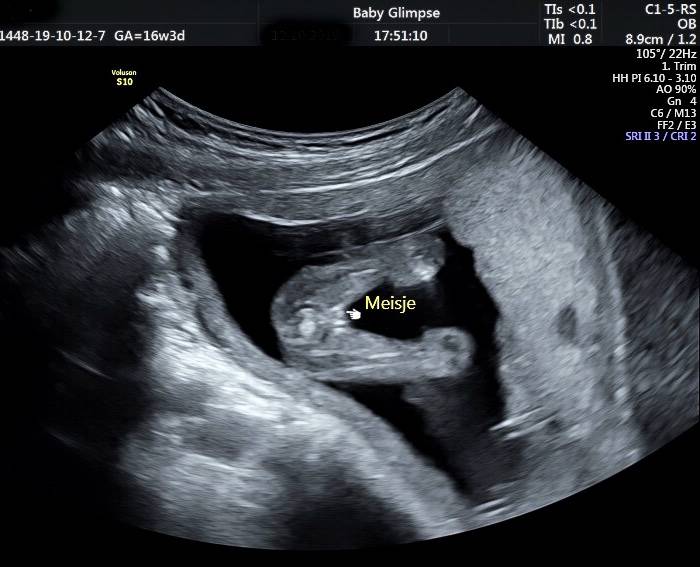

Wij maken jouw kennismaking magisch

Zwanger zijn is iets magisch. En dat prachtige gevoel willen wij nastreven in onze praktijk. Onze echoscopisten hebben een verloskundig achtergrond en werken daarnaast met de beste apparatuur. Ook hebben wij de leukste samenwerkingen met de mooiste merken waar jullie van kunnen profiteren. Dit alles zorgt voor een geweldige ervaring. Tot snel bij Baby Glimpse…